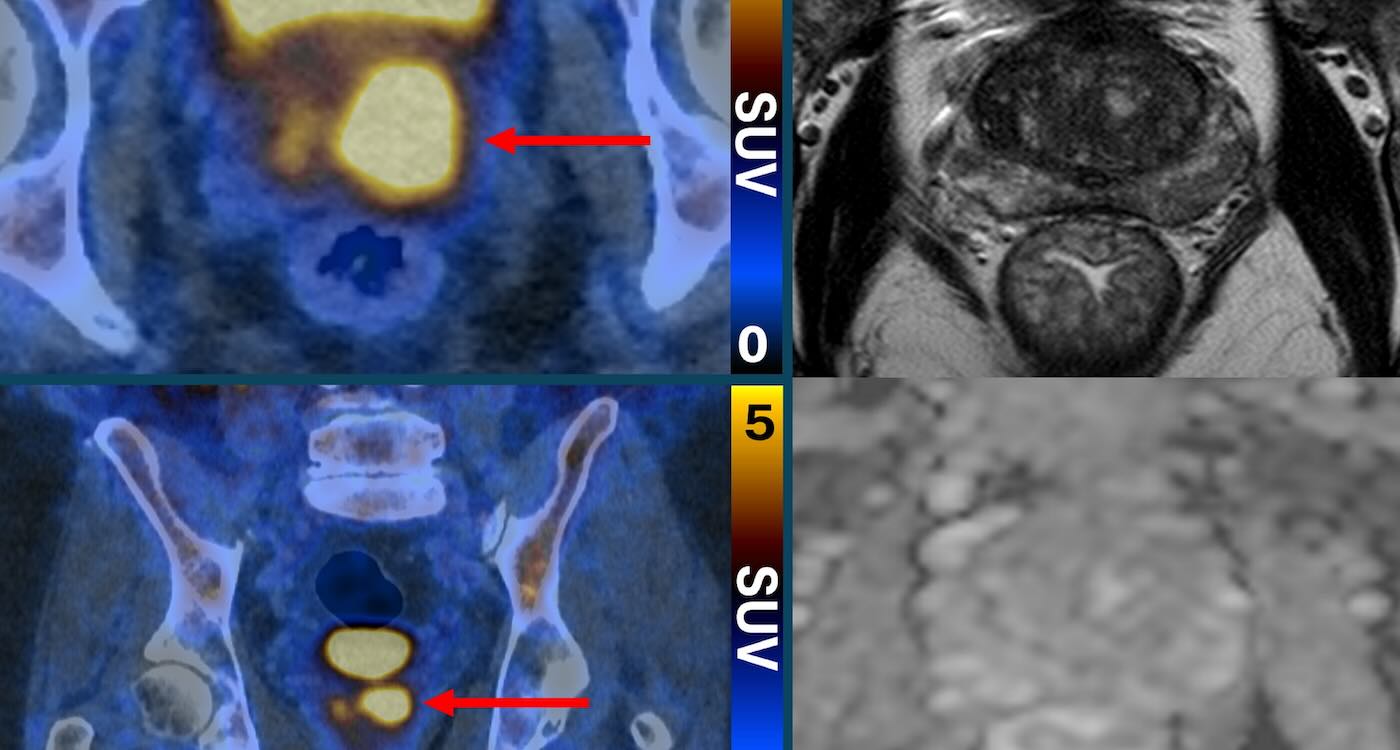

この新しいスキャン方法は、特別な分子を使って前立腺癌の細胞を明るく光らせるんだ。そうすることで、画像の中に明るい点が現れるの 🙌 これによって、より攻撃的な前立腺癌を見つけることができるし、低リスクの癌を見極めるのにも役立つの。

最近のPrimary2試験では、前立腺癌のリスクが高い男性が対象になって、2つのグループに分けられたんだ。一方は従来の生検、もう一方はこの新しい光るスキャンを受けたの。結果として、このスキャンで癌がないか、もしくは低リスクの癌が見つかった患者には生検が不要だったんだって!👍

2. 実施内容と成果

この研究を牽引した専門家は、前立腺癌のリスクを知らせることがどれほど不安の原因になるかを強調している。スキャンとMRIを組み合わせることで、「どの患者が本当に注意が必要か」を見極める手助けができるらしいよ📊